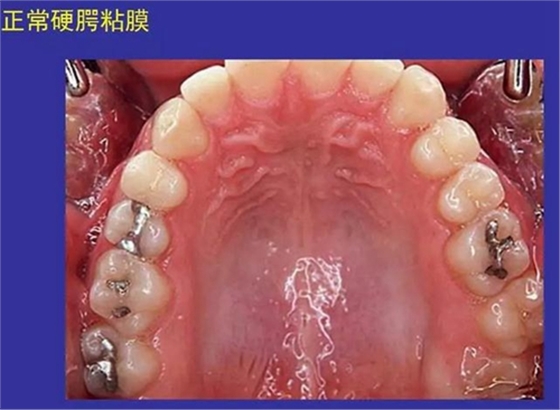

①口腔黏膜(oral mucosa):口腔內(nèi)的濕潤襯里

口腔黏膜感染性疾病及潰瘍類疾病圖示

一、口腔黏膜感染性疾病圖示